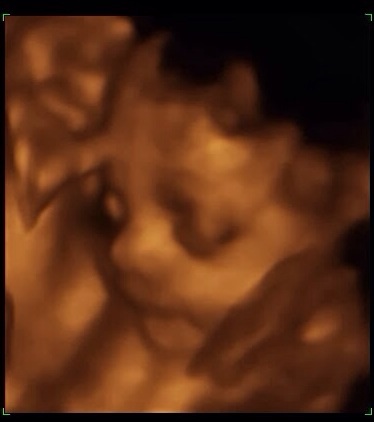

I updated on my post below that the scan went well and that he is adorable (so, so in love!).

Here's baby and grandpa to compare! I'll be poofing the picture of my grandfather later.

I think thats one of the best 3D u/s pictures i've seen!